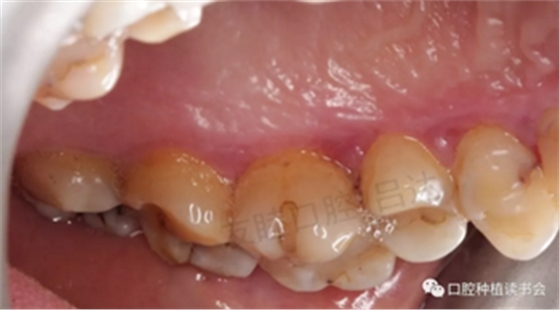

檢查視角轉(zhuǎn)向整個(gè)口腔,發(fā)現(xiàn)有廣泛牙周感染。齦乳頭處可探及齦下牙石,探診深度PD:4-6mm,出血指數(shù)BI:3-4。(圖5-圖10)

圖5 口內(nèi)牙周情況

圖6 左側(cè)上頜后牙區(qū)